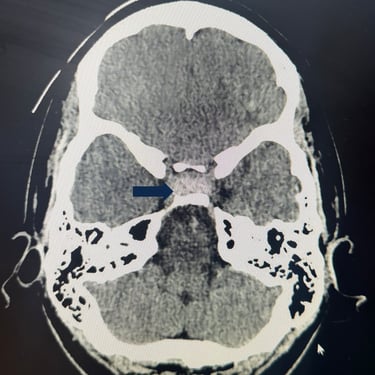

Tumor Selar Hemorrágico: Tratamiento Endoscópico Transesfenoidal.

El tumor selar hemorrágico, también conocido como apoplejía hipofisaria, es una urgencia neuroquirúrgica que puede manifestarse con cefalea intensa, alteraciones visuales y compromiso hormonal agudo. El abordaje mediante cirugía endoscópica transesfenoidal permite un acceso directo y mínimamente invasivo a la región selar, facilitando la evacuación del componente hemorrágico y la resección del tumor. Esta técnica ofrece una adecuada descompresión del quiasma óptico, preservación de estructuras neurovasculares y una recuperación más rápida. El tratamiento oportuno es clave para mejorar el pronóstico neurológico y visual del paciente.